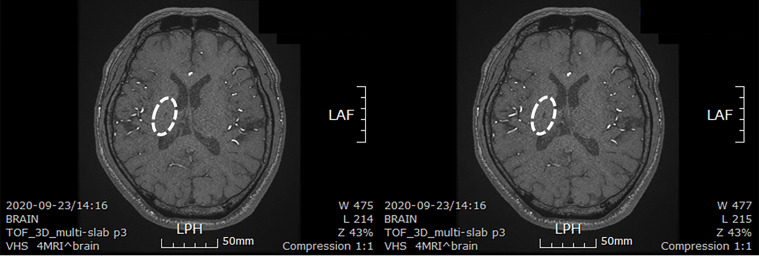

患者于2018年2月17日至18日出現暫時性無力癥狀,早上醒來后突發急性中風,導致左上肢和下肢癱瘓?;颊咴诖髮W醫院急診室被診斷為Rt紋狀體囊性梗死(圖1A)。他于2018年3月2日出院,僅接受了阿司匹林處方,因為根據腦計算機斷層掃描 (CT) 掃描,他的腦血管正常,盡管他的病情在住院期間惡化(圖1)。出院當天,他被送往康復專科醫院接受長期康復治療。然后他于2018年3月13日來韓國首爾生物美容與健康公司 (bBHC)-干細胞治療與研究所 (STRI)接受干細胞治療。

圖1:微創人臍帶間充質干細胞移植前患者的腦部計算機斷層掃描圖像。

圖1